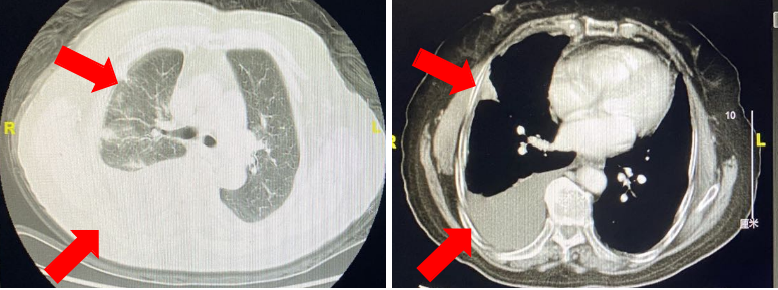

(2)二线免疫+化疗:PR

经患者充分知情同意并签署知情同意书后,考虑予以免疫联合化疗治疗。于2020年4月3日、2020年5月6日行“替雷利珠单抗200 mg+多西他赛q3w”治疗2周期,右肺多发病灶较前明显退缩,右侧胸腔积液减少,疗效评价;PR。患者用药期间未出现严重不良反应,至今仍在治疗中。

本例患者为右肺腺癌(TNM分期,IV期),伴右侧胸膜、叶间胸膜及右肺多发转移,驱动基因阴性。一线予以靶向联合化疗,疗效维持在SD,维持治疗16周期后复查提示病情进展。二线考虑予以免疫联合化疗,予以患者替雷利珠单抗联合多西他赛治疗2周期后,疗效即达PR,不良反应可控,患者生活质量高,二线PFS已超过5个月,且正不断延长中。